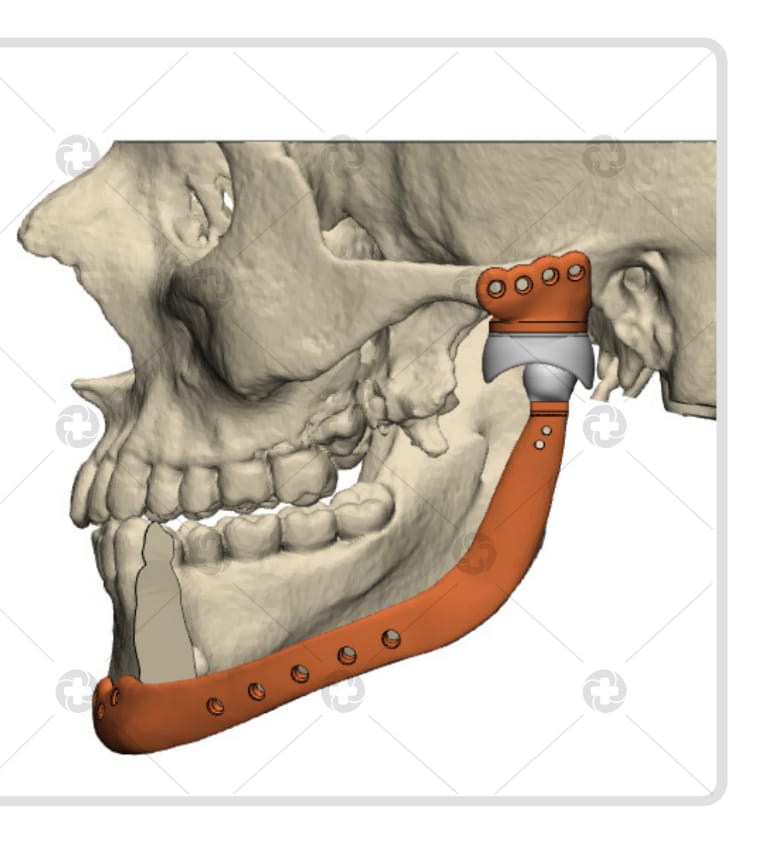

A cirurgia inédita consistiu na remoção do tumor “ameloblastoma”, um tumor agressivo, porém benigno, envolvendo estruturas nobres, como mandíbula e ATM. Com isso, foi feita a reconstrução com prótese customizada das duas estruturas perdidas, sendo a prótese em titânio.

O procedimento devolveu a função ao paciente, um adolescente de 17 anos, que sofria de dores frequentes, afetando diretamente a mandíbula direita.

O paciente permanecerá internado por sete dias, para maiores cuidados pós-operatórios e depois fará acompanhamento ambulatorial, com o cirurgião bucomaxilofacial e equipe multidisciplinar, envolvendo fonoaudiólogo e fisioterapeuta. Retornará ao convívio social, tendo restabelecidas a estética facial, função mastigatória e a fala.